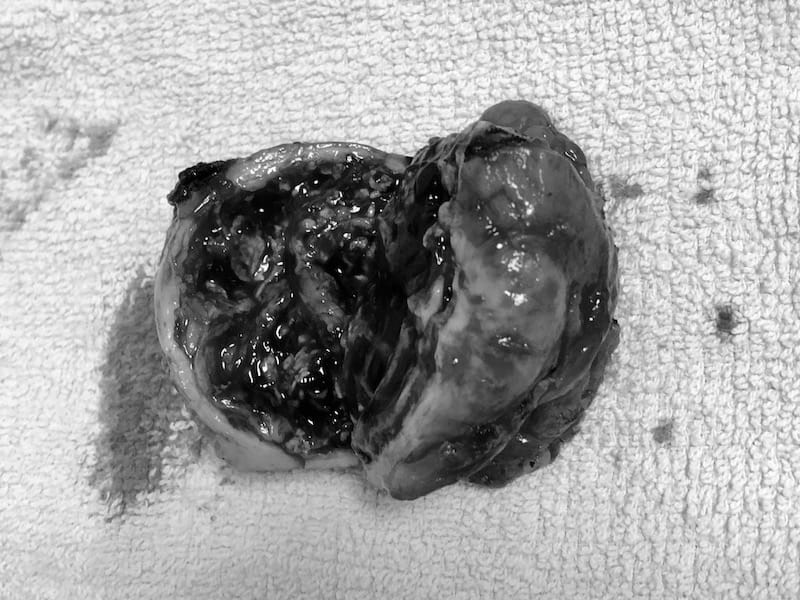

13:20 手術完成,醫生跟我老婆說明,給她看我的腫瘤(好像一顆多子的熱帶水果)。